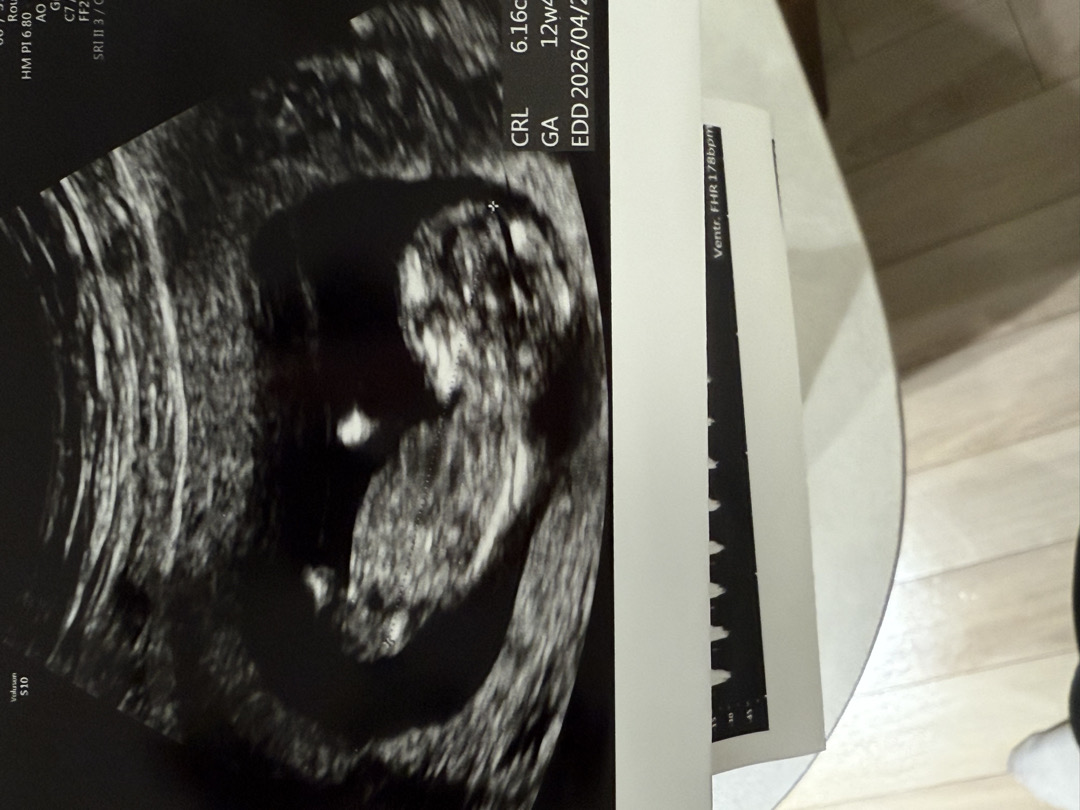

각도법으로 성별 한번 골라주세요

딸인지 아들인지 감이 안와요 다들 저한테 아들맘 상이라고 하고 태몽도 아들 관련된거라는데,, 봐주세요